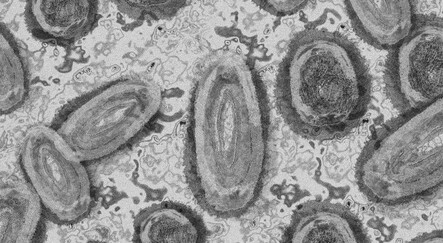

AB maymun çiçeği aşısına onay verdi

Avrupa Birliği (AB) maymun çiçeği virüsüne karşı Danimarkalı biyoteknoloji şirketine onay verdi. Hollanda'da ise risk grubundaki bireyler için maymun çiçeği virüsüne karşı aşılamaların başladığı bildirildi.

DSÖ'nün acil durum ilan etmesinin ardından AB, maymun çiçeği virüsü aşısına satış izni verdi. AB Komisyonundan alınan bilgiye göre, Bavarian Nordic'e (BAVA.CO) maymun çiçeği aşısı için pazarlama izni verildi.